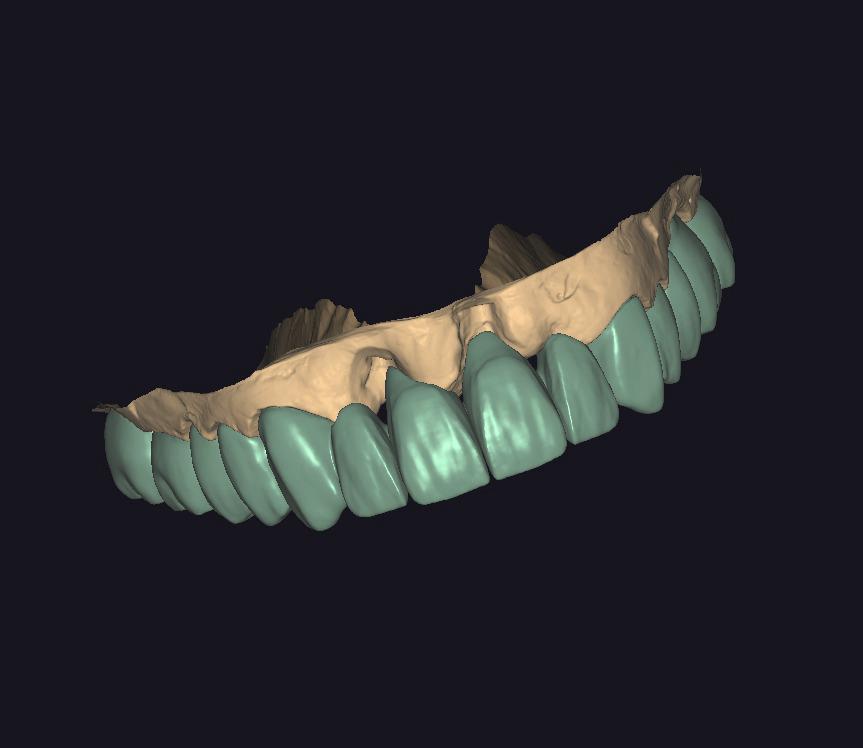

ZIRKONYUM

ZIRKONYUM ALT YAPI

IMPLANT USTU ZIRKONYUM

IMPLANT USTU ZIRKONYUM ALT YAPI